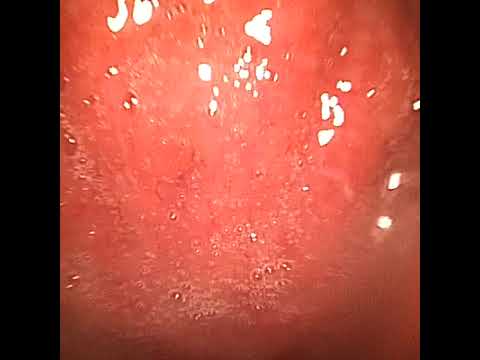

Видео: Передняя риноскопия

С помощью специализированных инструментов врач проводит диагностику, выявляющую скрытые заболевания. Риноскоп позволяет исследовать носовую раковину, перегородку и клиновидную пазуху. В дополнение к риноскопу используются эндоскоп с камерой и специальные зеркала.

Риноскопия — это диагностическая процедура, позволяющая отоларингологам исследовать полость носа и носоглотку. Это обследование важно для выявления заболеваний, таких как синуситы, полипы, аллергические реакции и опухоли. Процедура выполняется с использованием риноскопа, который обеспечивает четкое изображение слизистой носа.

Риноскопия является важным диагностическим методом, который позволяет врачам-отоларингологам оценить состояние носовой полости и придаточных пазух. Эксперты отмечают, что данная процедура помогает выявить различные заболевания, такие как синуситы, полипы и опухоли. В ходе риноскопии врач использует специальный инструмент — риноскоп, который позволяет визуально осмотреть слизистую оболочку носа.